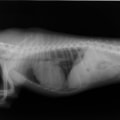

症例6:【ACVIM StageD ビーグル 10歳 去勢雄】

A:胸部レントゲン写真 側面像

左側胸壁心尖部領域を最強点とするLevine 5/6の収縮期性心雑音が聴取された。安静時にも咳が認められる。胸部レントゲン検査において重度の心拡大が及び肺水腫が認められた。超音波検査では、重度の僧帽弁閉鎖不全、三尖弁閉鎖不全が認められた。三尖弁逆流速度から肺高血圧症が示唆された。ACE阻害薬、ピモベンダン、硝酸イソソルビド徐放剤、ベラプロストナトリウム、利尿剤としてフロセミド及びスピロノラクトンを用いて治療を行っている。